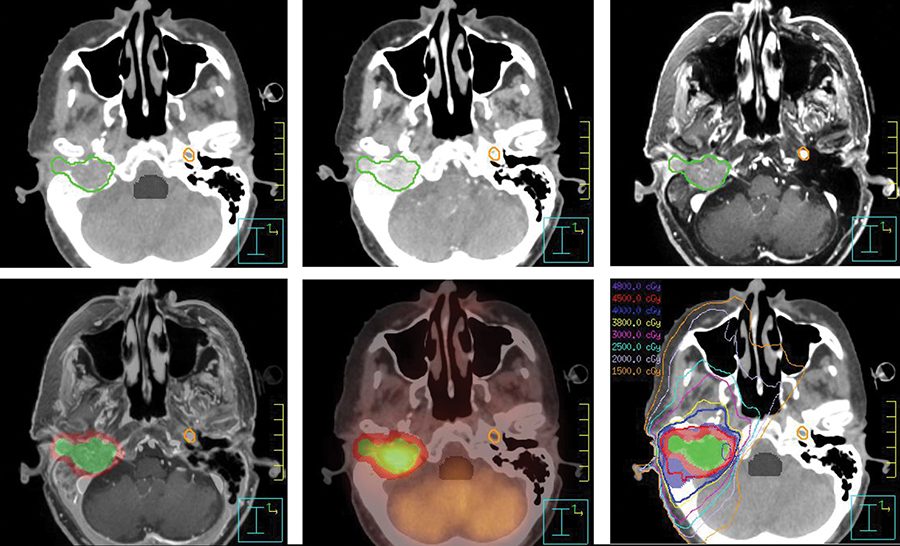

Supratentorial Tumors in the Pediatric Population ...

Supratentorial Tumors in the Pediatric Population ... from neupsykey.com